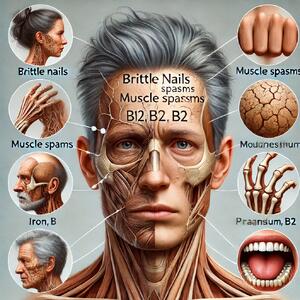

علائمی که از کمبودهای تغذیهای در بدن خبر میدهند - سبک ایده آل

بدن با علائمی مانند شکستن ناخن، اسپاسم عضلانی و سفید شدن مو، کمبود ویتامینها و املاحی چون B12، منیزیم و آهن را نشان میدهد.